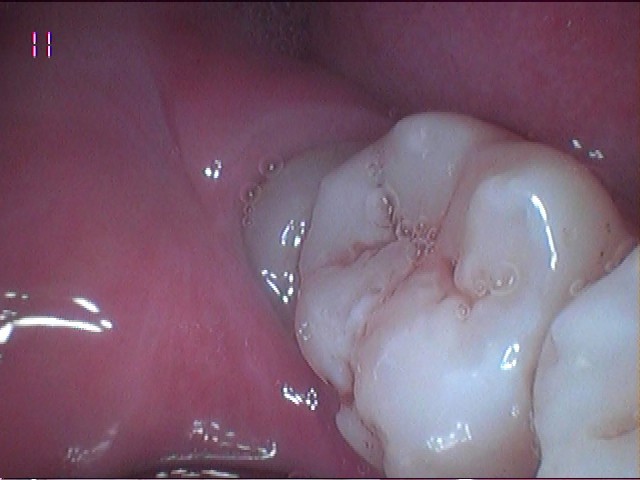

智齒阻生

智慧牙阻生是指最後一顆大磨牙未能完全穿透牙齦萌出,被困在頜骨或牙齦組織下的情況。這種情況在智齒(即第三顆磨牙)中常見,智齒通常在青少年晚期或成年早期(17-25嵗)長出。了解阻生磨牙的起因、症狀、潛在併發症和治療選擇對於維護口腔健康至關重要。

腫脹和發炎:被困牙齒周圍的牙齦可能腫脹,伴隨紅腫和觸痛。